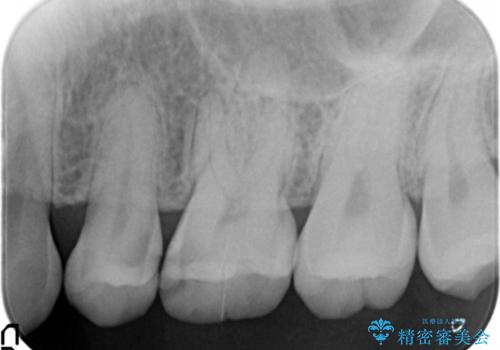

- 検診で当院を受診され、X線写真検査により大きな虫歯が見つかった症例です。

歯の種類、かかると予想される咬合力負担、残存歯質、審美性等々を考慮し審美的なセラミックインレー、力に強いゴールドインレーをそれぞれ選択し修復を行いました。